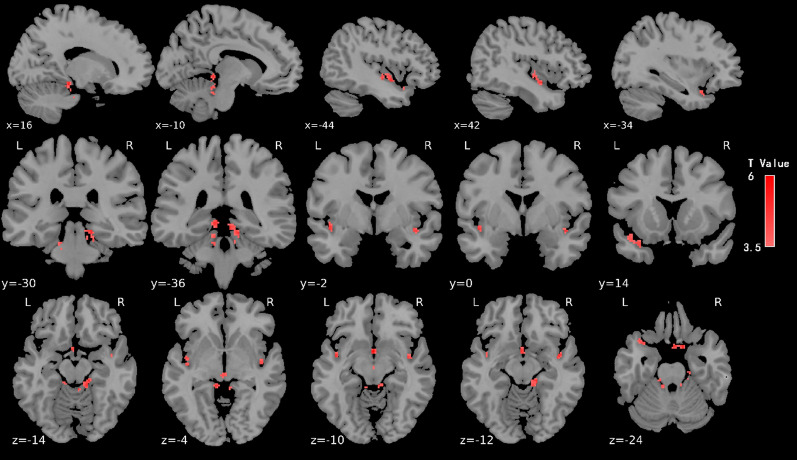

Neuroplasticity, a phenomenon present throughout the lifespan, is thought to be influenced by physical training. However, the relationship between neuroplastic differences and attentional abilities remains unclear. This study explored the differences in brain function and attentional abilities between professional football athletes and novices, and further investigated the relationship between the two. To address this question, we included 49 football athletes and 63 novices in our study, collecting data on resting-state functional connectivity and Attention Network Test (ANT). Behavioral results from the ANT indicated that football experts had superior orienting attention but weaker alerting functions compared to novices, with no difference in executive control attention. fMRI results revealed that football experts exhibited higher fractional Amplitude of Low-Frequency Fluctuations (fALFF) values in the bilateral anterior cerebellar lobes, bilateral insula, and left superior temporal gyrus. Functional connectivity analysis showed increased connectivity between the left anterior cerebellar lobe and various cortical regions, including the right supramarginal gyrus, left precuneus, left superior frontal gyrus, bilateral posterior cerebellar lobes, and bilateral precentral gyri in experts compared to novices. More importantly, in the expert group but not in novice group, functional connectivity differences significantly predicted attentional orienting scores. Graph theoretical analysis showed that experts exhibited higher betweenness centrality and node efficiency in the right cerebellar lobule III (Cerebelum_3_R) node. Our findings demonstrate that long-term professional football training may significantly affect neuroplasticity and attentional functions. Importantly, our analysis reveals a substantive connection between these two aspects, suggesting that the integration of neuroplastic and attentional changes is likely mediated by cerebellar-cortical connectivity.